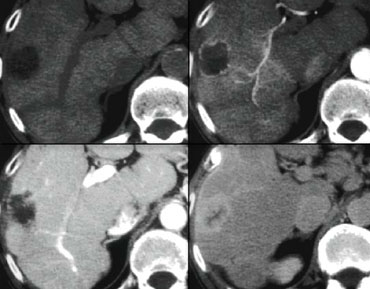

NECT, arterial and portal venous phase in a patient with Hepatitis C with two lesions in the liver (arrows). NECT, arterial and portal venous phase in a patient with Hepatitis C with two lesions in the liver (arrows).

In the arterial phase we see two hypervascular lesions.

Now do not just concentrate on the images, where you see the lesions best.

You have to look at all the other images, because they give you the clue to the diagnosis.

The upper images show a lesion that is isodens to the liver on the NECT.

In the arterial phase there is enhancement, but not as dense as the bloodpool.

In the portal venous phase the lesion is again isodense to the surrounding liver parenchyma and you can't see it.

If you only had the portal venous phase you surely would miss this lesion.

The lower images show a lesion that is visible on all images.

You see it on the NECT and you could say it is hypodens compared to the liver.

Does this help you?

No, not in the least.

However if you look at the bloodpool, you will notice that on all phases it is as dense as the bloodpool.

So we have a HCC in the right lobe on the upper images and a hemangioma in the left lobe on the lower images.

The key is to look at all the phases.